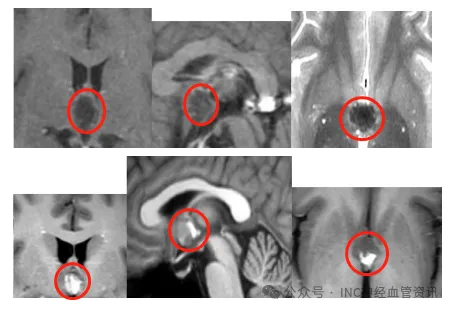

26歲青年高原返程后頭痛兩月未愈,一查竟是第三腦室“潛伏”的海綿狀血管瘤

那天,阿浩結束高原旅程回家,但身體的異常感并未隨著旅行的結束而消失。頭痛、頭暈持續(xù)困擾著他,這種不適感與普通的高原反應不同,可癥狀持續(xù)兩個月不見好轉,一種強烈的不安讓他踏...